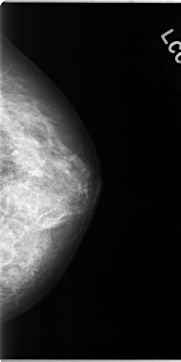

C_0127_1.LEFT_MLO

C_0127_1.LEFT_CC

LEFT_MLO LINES 4712 PIXELS_PER_LINE 2416 BITS_PER_PIXEL 12 RESOLUTION 50 NON_OVERLAY

LEFT_CC LINES 4696 PIXELS_PER_LINE 2352 BITS_PER_PIXEL 12 RESOLUTION 50 NON_OVERLAY